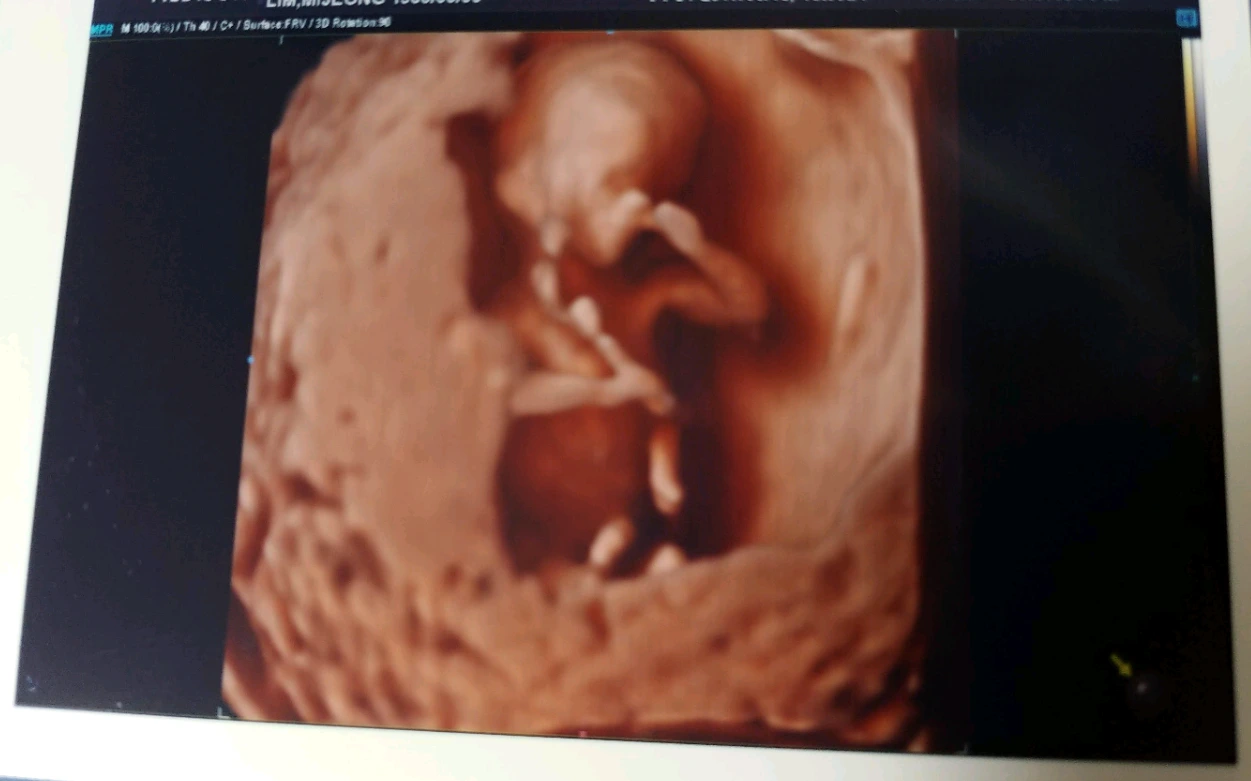

아기는 오늘로 정확히 13주가 되었다.

오늘은 정밀초음파를 하는 날이었다. 기형아 여부를 판별하기 위해 정밀 초음파로 목덜미 두께를 재는 것인데, 모든 임산부가 겪는 과정이겠지만 그러지 않으려고 해도 여러 근심과 걱정이 떠오른다. 다운증후군이라면, 척추관 기형이나 다른 생각도 못한 문제가 있다면 어떻게 되는 걸까.

정밀초음파를 보는 곳이라 평소와 다른 진료실이었다. 검사할 준비가 되자 의사가 커튼을 열고 들어온다. 해상도가 높은 초음파로 아기 몸의 구석구석을 확인하는데 꽤 많은 시간이 걸렸다.

곰돌이처럼 둥글둥글하기만 한 2주 전 체형과는 많이 다르다. 구부리고 있는 무릎관절이 꽤나 정교해 보였고, 쭉 펼친 다섯 개 손가락도 선명하다. 녀석은 자궁벽에 등을 기대고 꽤나 편안한 듯 둥실 거리다가, 갑자기 우리를 향해 돌아눕기도 했다.

초음파를 조작하자 아기의 모양이 입체로 구성되었다. 이목구비가 제법 보인다. 태아 사진을 보고 잘 생겼네 마네 하는 엄마들의 이야기에 코웃음을 쳤었지만 오늘 보니 내 아기는 진심으로, 잘 생겼다고 생각했다. 자세한 이목구비는 알 수 없지만 위치한 각 자리의 비율이 훌륭하다.

나는 혼자 조용히 ‘엄마 미소’를 지었다. 발달도 좋고, 목덜미 두께도 정상이다. 확인 가능한 기관들은 모두 정상 소견이다. 눈물이 나려는 걸 보니 내가 은근히 걱정을 많이 했었구나 하는 생각이 든다.